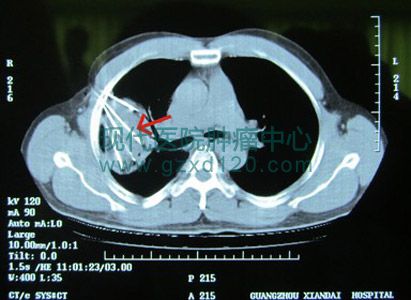

针对该患者病情及CT、病理检查结果,广州现代医院组织专家团会诊,诊断为:1、右肺中分化鳞癌伴纵隔淋巴结转移,属于ⅢA期;2、糖尿病;3、囊结石;4、肺部s感染。体质很差,传统治疗已经没有意义,以致被菲律宾当地医院认为“不治”。

她至今印象深刻:“太神奇了,四根管子插到肺部肿瘤上,医生首先输入氩气,嘶嘶地响个不停。通过CT显示,看到肺部肿瘤形成一个冰球,冰球很大很硬,因为肿块有10×12×13厘米那样大。过了十五分钟后,改输入另一种叫氩气的气体。连续做了两个循环,一个钟不到就完成手术。医生告诉我,说整个肿瘤组织都冰球包住了,里面的肿瘤细胞坏死率达到80%。手术时,他不像以前那样喊疼,做完后觉得针口微疼,第二天就不痛了。我们感觉中国医疗技术很强大很先进。”

右肺部肿块巨大,有10×12×13厘米

4支氩氦刀导管插入肿块形成冰球,冰球内肿瘤细胞坏死率达到80%